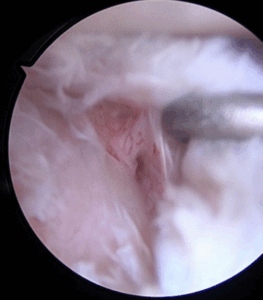

It was demonstrated that, despite the different concave shape of the glenoid, its OCD follows the same progression over the time of the convex weight-bearing articular surfaces and needs, likewise, the same gradespecific management. Patients with IRCS OCD stage I and some with OCD stage II present with a stable shoulder and can undergo conservative treatment. Unstable or advanced glenoid OCD stages, characterized by disruption of the articular cartilage and the presence of separated fragments as loose bodies, require surgical treatment. Moreover, this is indicated when the conservative approaches fail, especially because of long-standing pain and joint range of motion worsening. Proposed surgical treatments include arthroscopic drilling, microfractures, debridement of the unstable osteochondral fragments, and fixation with suture anchor or autogenous osteochondral plugs, platelet-rich plasma, and gellike sodium hyaluronate. (2,4) There is not yet consensus regarding the ideal technique. In this Technical Note, we describe an arthroscopic procedure with a single-layer hyaluronate-based scaffold for the treatment of OCD of the glenoid.